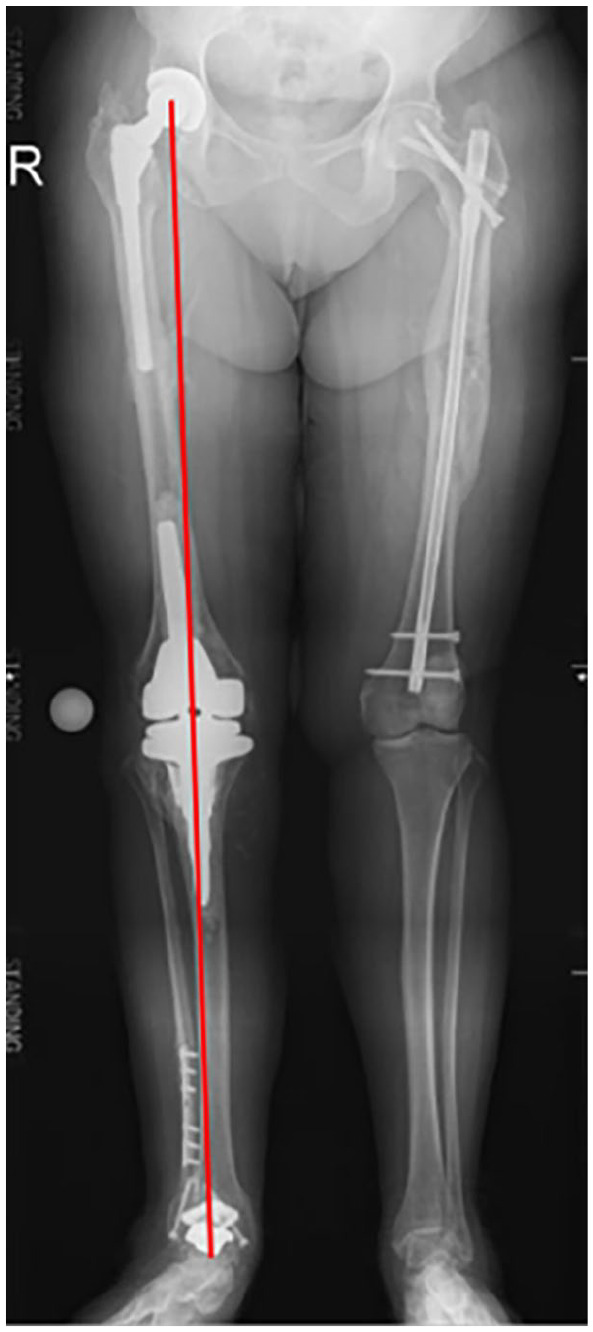

Background: Total knee arthroplasty (TKA) and hindfoot reconstruction (HFR) are often used to treat osteoarthritis and deformities of the knee and hindfoot. Despite the proven clinical effectiveness of these treatments, postoperative patient dissatisfaction is high. The knee and ankle are adjacent joints in the lower extremity, and angular deformity of either joint is known to affect positioning of the anatomical and mechanical axes of the entire limb. Although it is understood this relationship exists, there are limited studies evaluating outcomes of ipsilateral procedures on patients with pathologies of both knee and hindfoot. This article aims to evaluate whether TKA or TAA/HFR sequencing influences postoperative outcome. The study hypothesis is that TKA prior to TAA/HFR results in lower reoperation.

Abstract Image